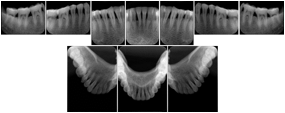

6 Standard + 4 Bitewing C Dental Image Layout

DL-P002E

Reference:

01

Standard

11, 12, 21, 22

11

32, 31, 41, 42

20

Bitewing

18, 17, 16, 15, 48, 47, 46, 45

21

17, 16, 15, 14 47, 46, 45, 44

23

27, 26, 25, 24, 37, 36, 35, 34

24

28, 27, 26, 25, 38, 37, 36, 35